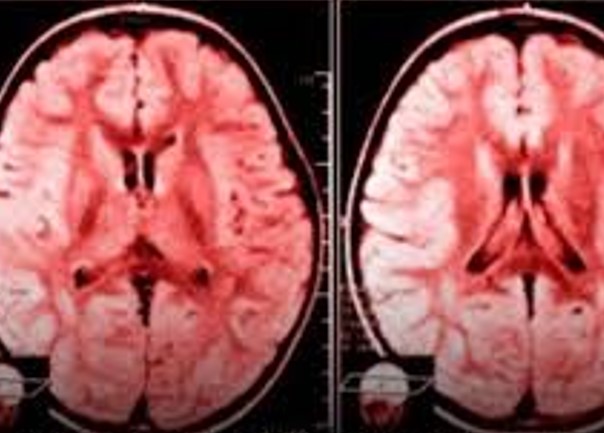

Esse processo é conhecido como neuroplasticidade negativa: quanto mais você pratica um pensamento ou comportamento, mais o cérebro se organiza para repeti-lo.

- enfraquece áreas do cérebro ligadas à memória e à tomada de decisão (como o hipocampo e o córtex pré-frontal),